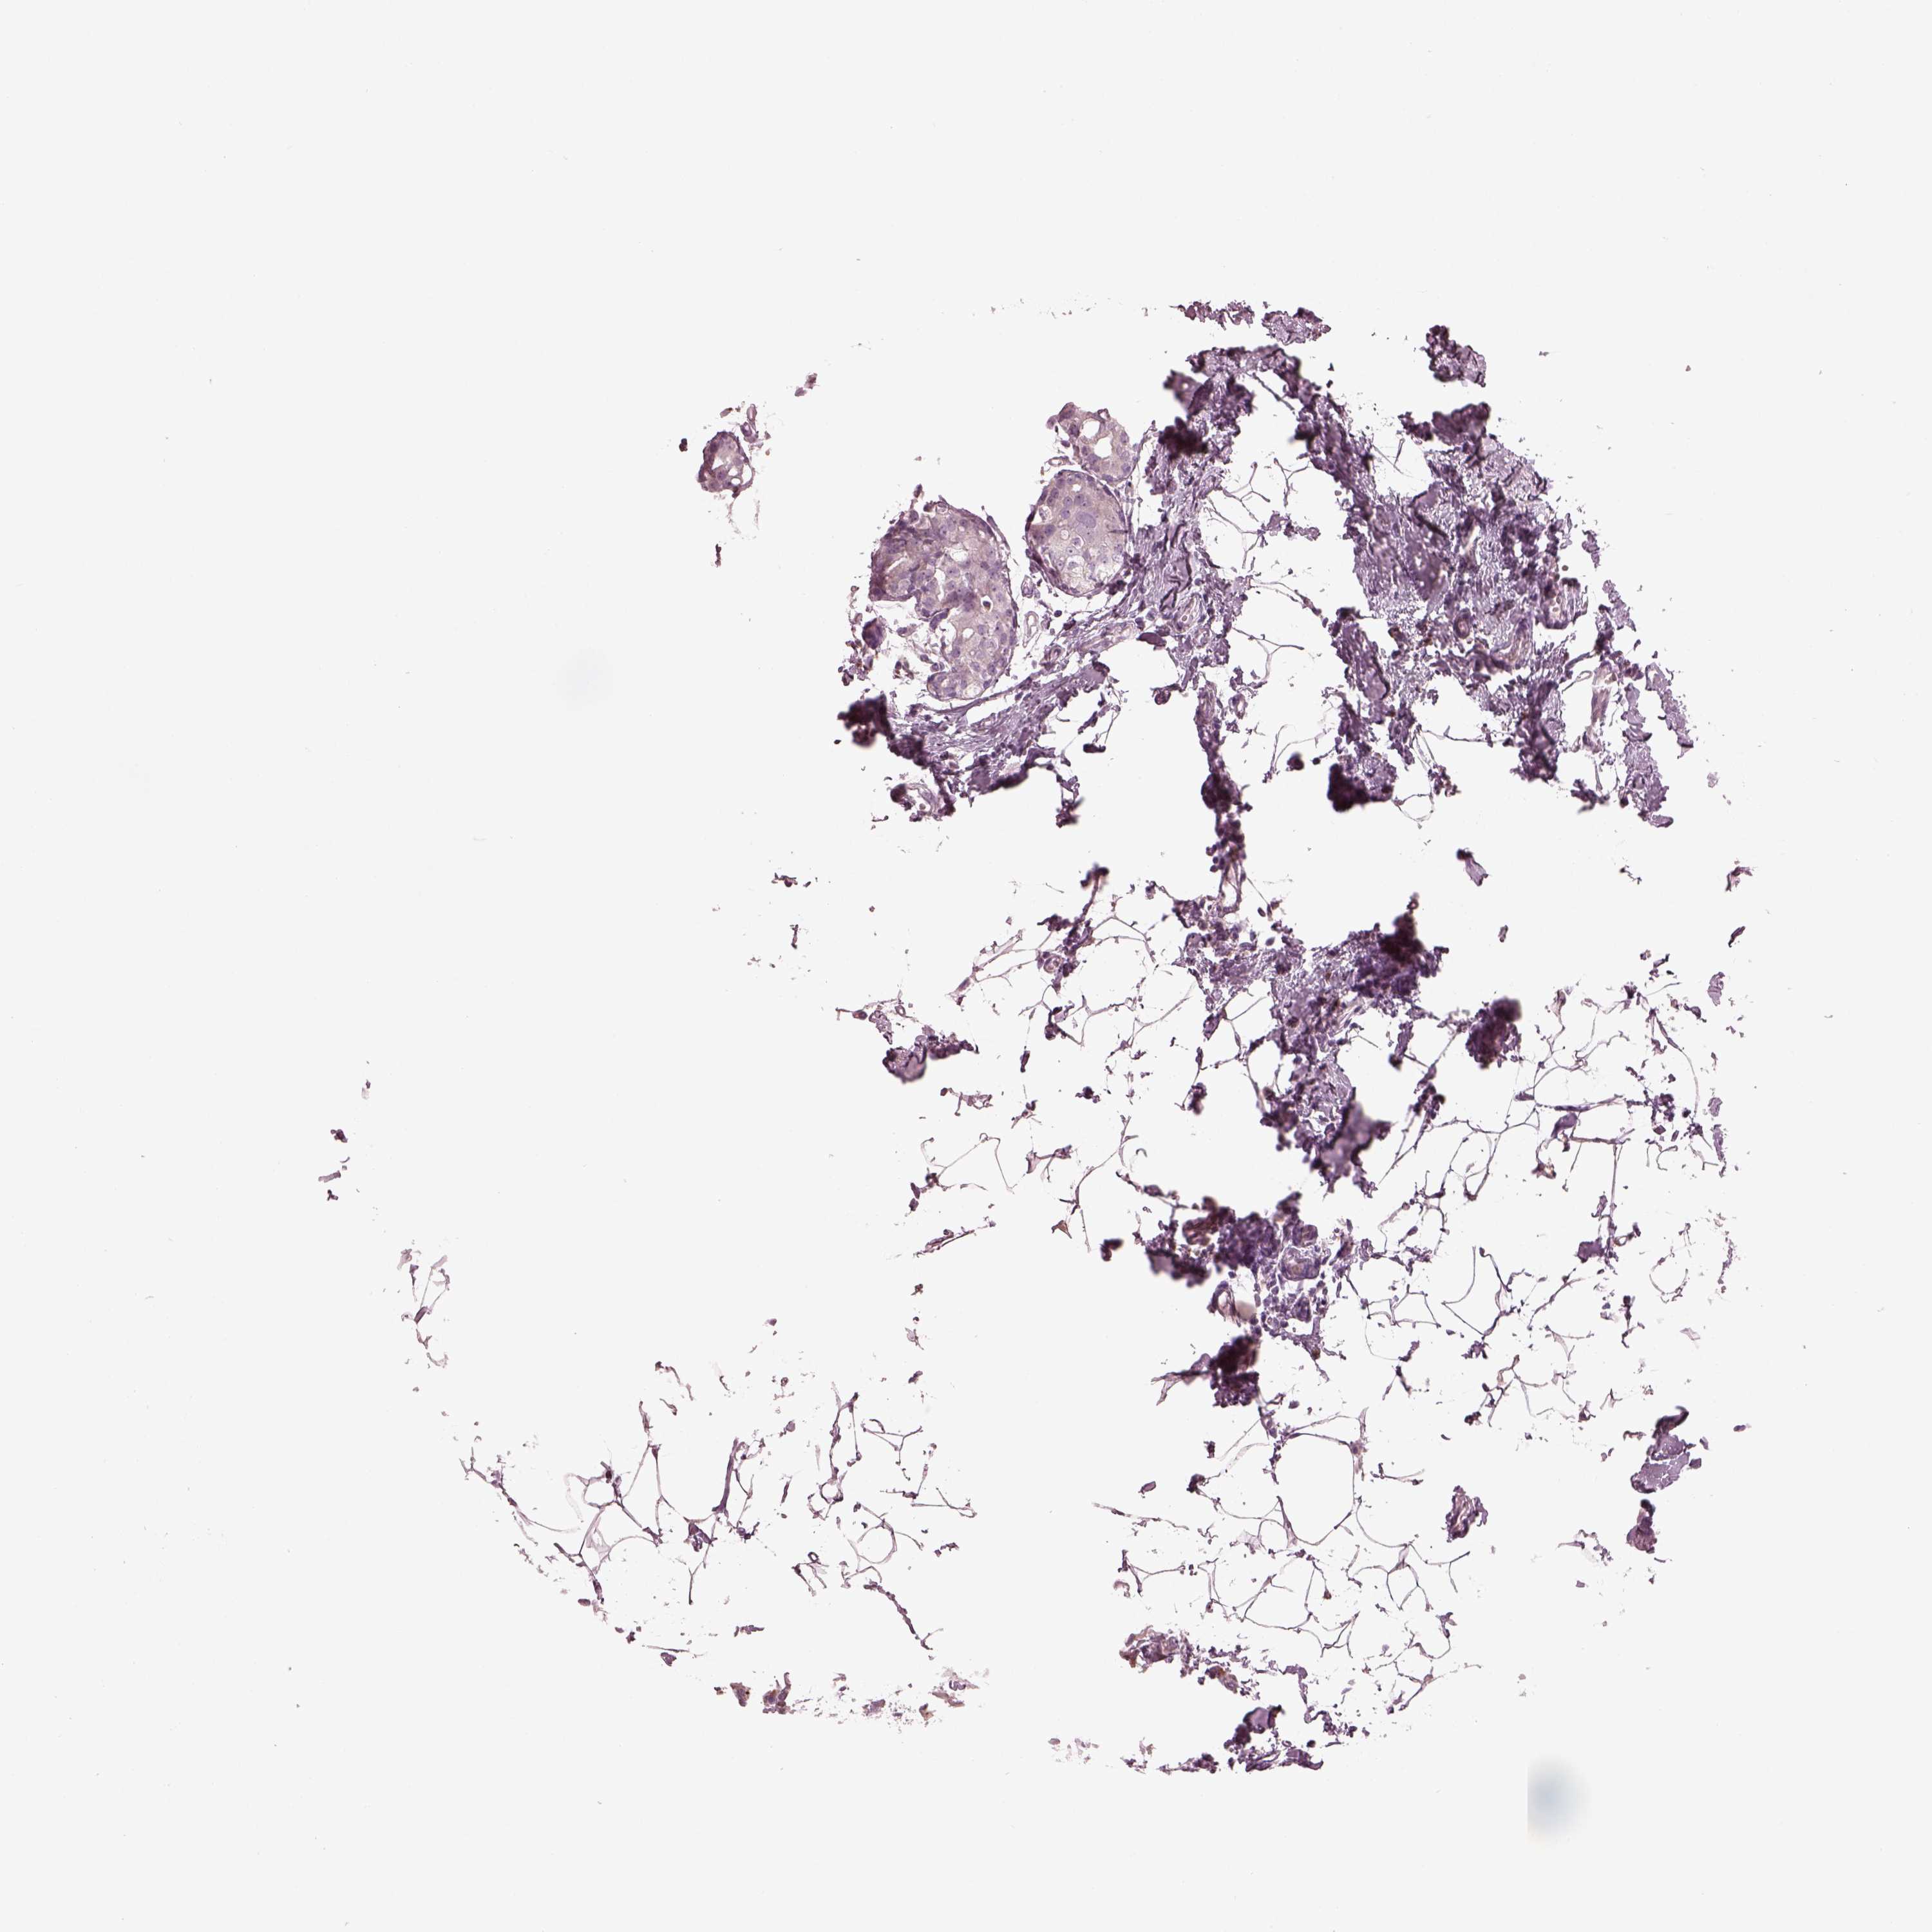

CANCER BREAST CANCER Show tissue menu

BRCA TCGA BRCA VALIDATION PROTEIN EXPRESSION

Breast cancer

Human cancer